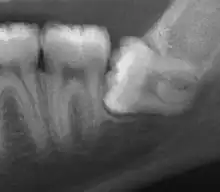

| Impacted wisdom tooth with a horizontal orientation | |

| Diagnostic method | X-rays, CT scans |

An ectopic tooth, also known as an impacted tooth, is a tooth that develops in an abnormal position and fails to erupt into its normal location in the oral cavity. [1] [2] Ectopic teeth can cause a variety of symptoms, such as pain, swelling, and infection, and they can lead to more serious complications if left untreated.

Diagnosis of ectopic teeth typically involves a comprehensive dental examination, including X-rays and other imaging tests. Treatment options for ectopic teeth depend on the location and severity of the condition, as well as the age and overall health of the patient. In some cases, observation and monitoring may be sufficient, while in other cases, surgical intervention may be necessary to remove the ectopic tooth and prevent further complications.[5]